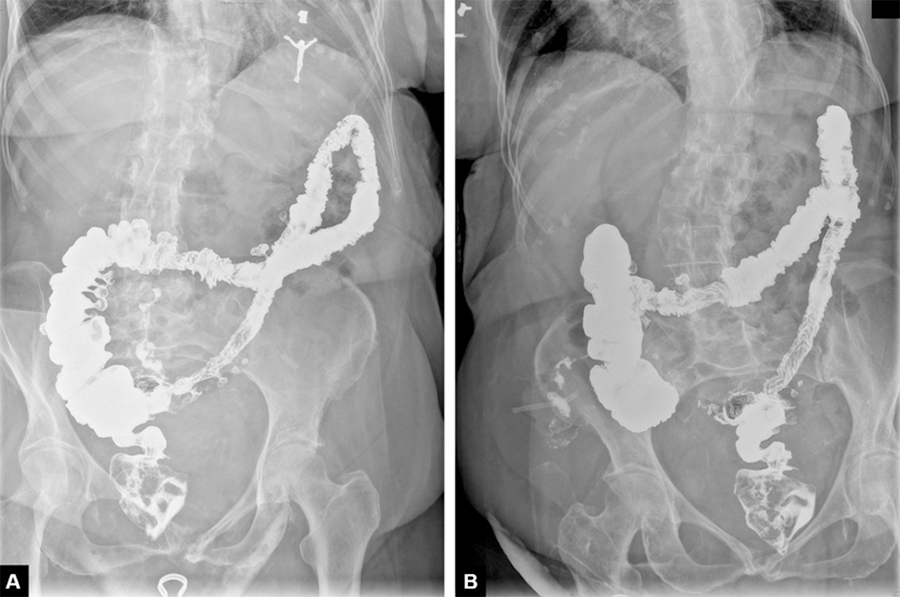

An initial plain radiograph of the chest showed a right upper quadrant lucency and could not rule out pneumoperitoneum. A computed tomography (CT) scan of the abdomen and pelvis without contrast showed a large encapsulated gas collection in the anterior right lower quadrant with fluid layering posteriorly, a small volume pneumoperitoneum in the right upper and lower quadrants, and abundant colonic diverticula (Figure 1). Laboratory results revealed leukocytosis of 16,100 cells per microliter (normal: 3,400-9,600). Hemoglobin and lactate measurements were within normal limits.

Figure 1. CT Scan of Abdomen and Pelvis Showing Right Adnexal Gas Encapsulation With Small Pneumoperitoneum in Coronal (A, B) and Transverse (C, D) Views. Published with Permission